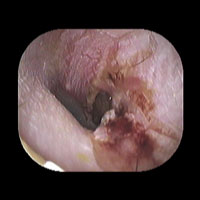

右急性中耳炎(重症) 鼓膜切開

鼓膜が赤く腫れて、鼓膜の奥に白い膿がたまっています。高熱が続き、痛みがとても強かっため、鼓膜切開を行いました。

9日目にほぼ治りました。当院ではできる限り鼓膜切開を行わずに治すことを考えていますが、必要な時はお勧めしています。

初診時 鼓膜切開の直前